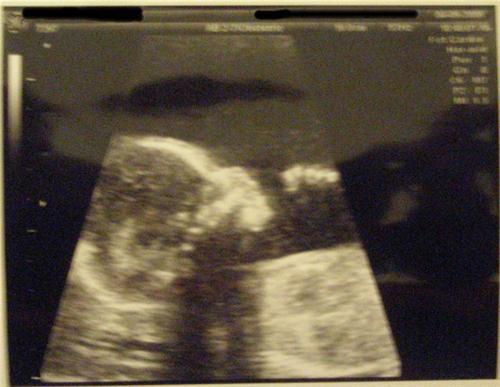

The Level 2 went well. Ed-lie Bubbles is measuring right on target. She is very healthy and moving around - tumbling and kicking - so much so that I may give her the last name "Tynes" in honor of the Giants' kicker who got them into the Superbowl. Here she is again:

THE MONEY SHOT:

Pretty bedding and great sono shots!!! There is no denying there is a girl inside your belly

what an Ed-lie filled day! The sono pictures are so great... I can't wait until our level II....

Looks great!!!! You have a thumb sucker!!!